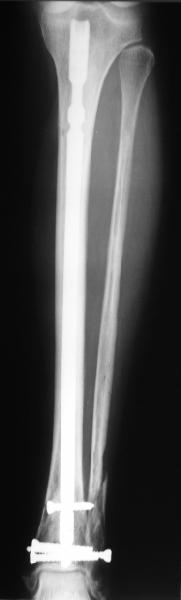

Проксимальный и дистальный переломы tibia

Направили к нам пациентку 35 лет с переломом дистального отдела костей голени.

У нас сделали снимок сзахватом обоих суставов - еще и проксимальный метафиз сломан. Чем бы у вас фиксировали такой перелом? Как его правильно закодировать по классификации АО?

Alexander Chelnokov 22 Май 2006, 00:35

Сделали все-таки стержнем. На всякий случай просверлил дополнительное проксимальное отверстие, так что получилось три 45-градусных винта.

В дистракторе провеи спиц поболше в прокисмальном отделе, чтобы не разобщить фрагменты при сгибании колена. Комментарии и критика приветствуются.

We proceeded with nailing using a small wire distractor, with few wires at the proximal end to prevent displacement with forced knee flexion. Images attached. Comments and critics are welcome.